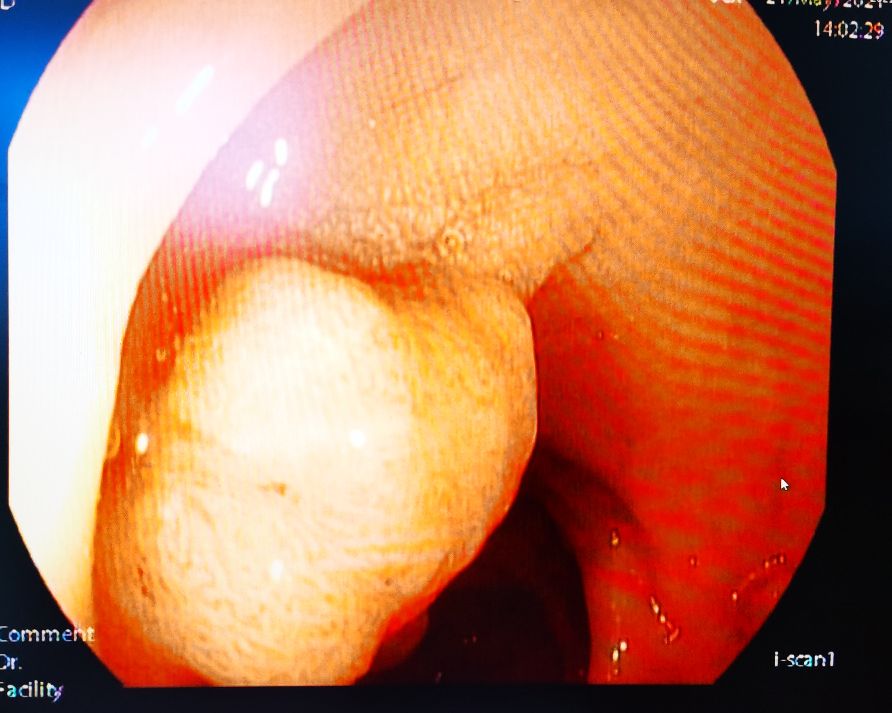

肠镜下直肠息肉